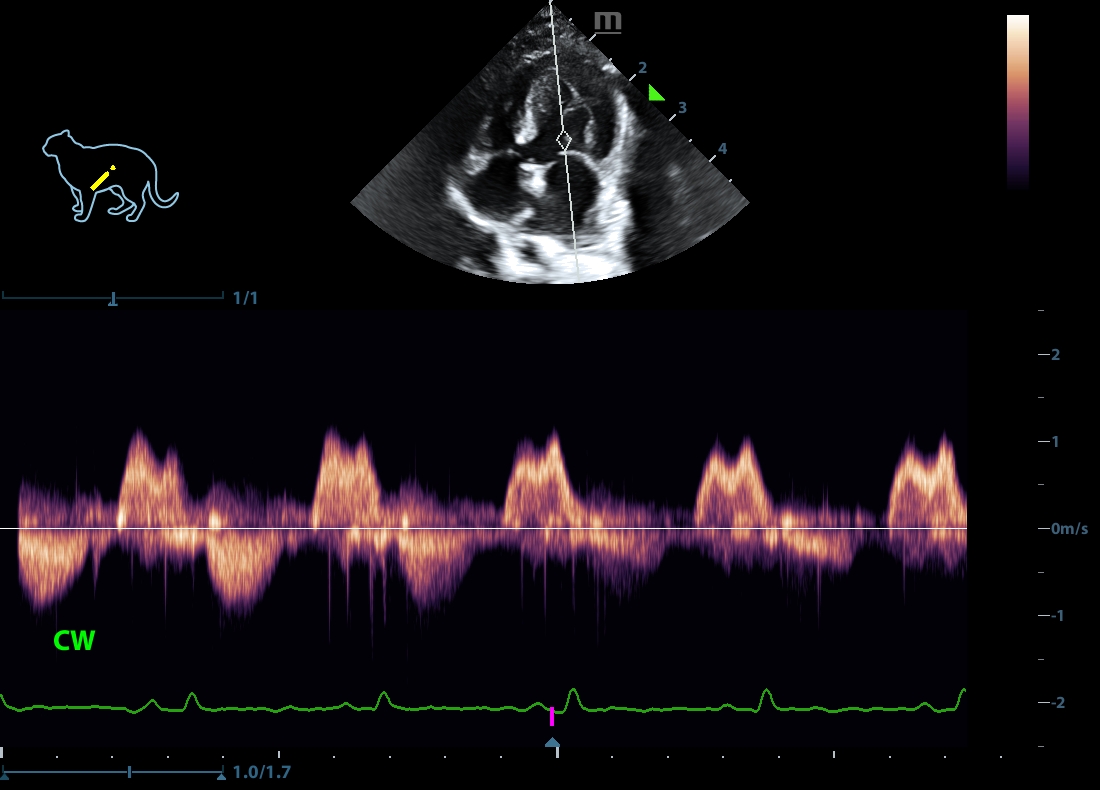

202505170048590154CARD.JPG